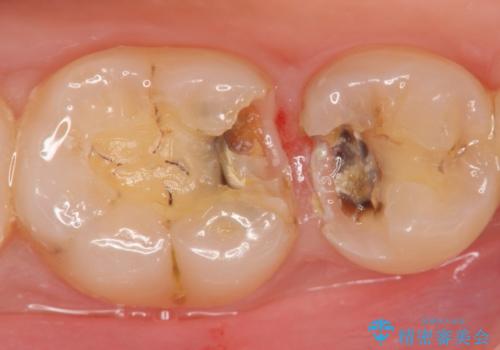

X線撮影を行った結果、詰めた箇所の下部に虫歯の再発を認めました。

再発した虫歯は神経に近いことが多く、丁寧に除去することで神経を温存し、精密なセラミック修復を行うことで更なる虫歯の再発を防ぎます。

虫歯治療後の虫歯の再発は、神経の治療(根管治療)が必要になることも多くなってしまいます。

虫歯の再発を防ぐよう、しっかりと虫歯を除去すること、削り取った部分を封鎖することが重要です。